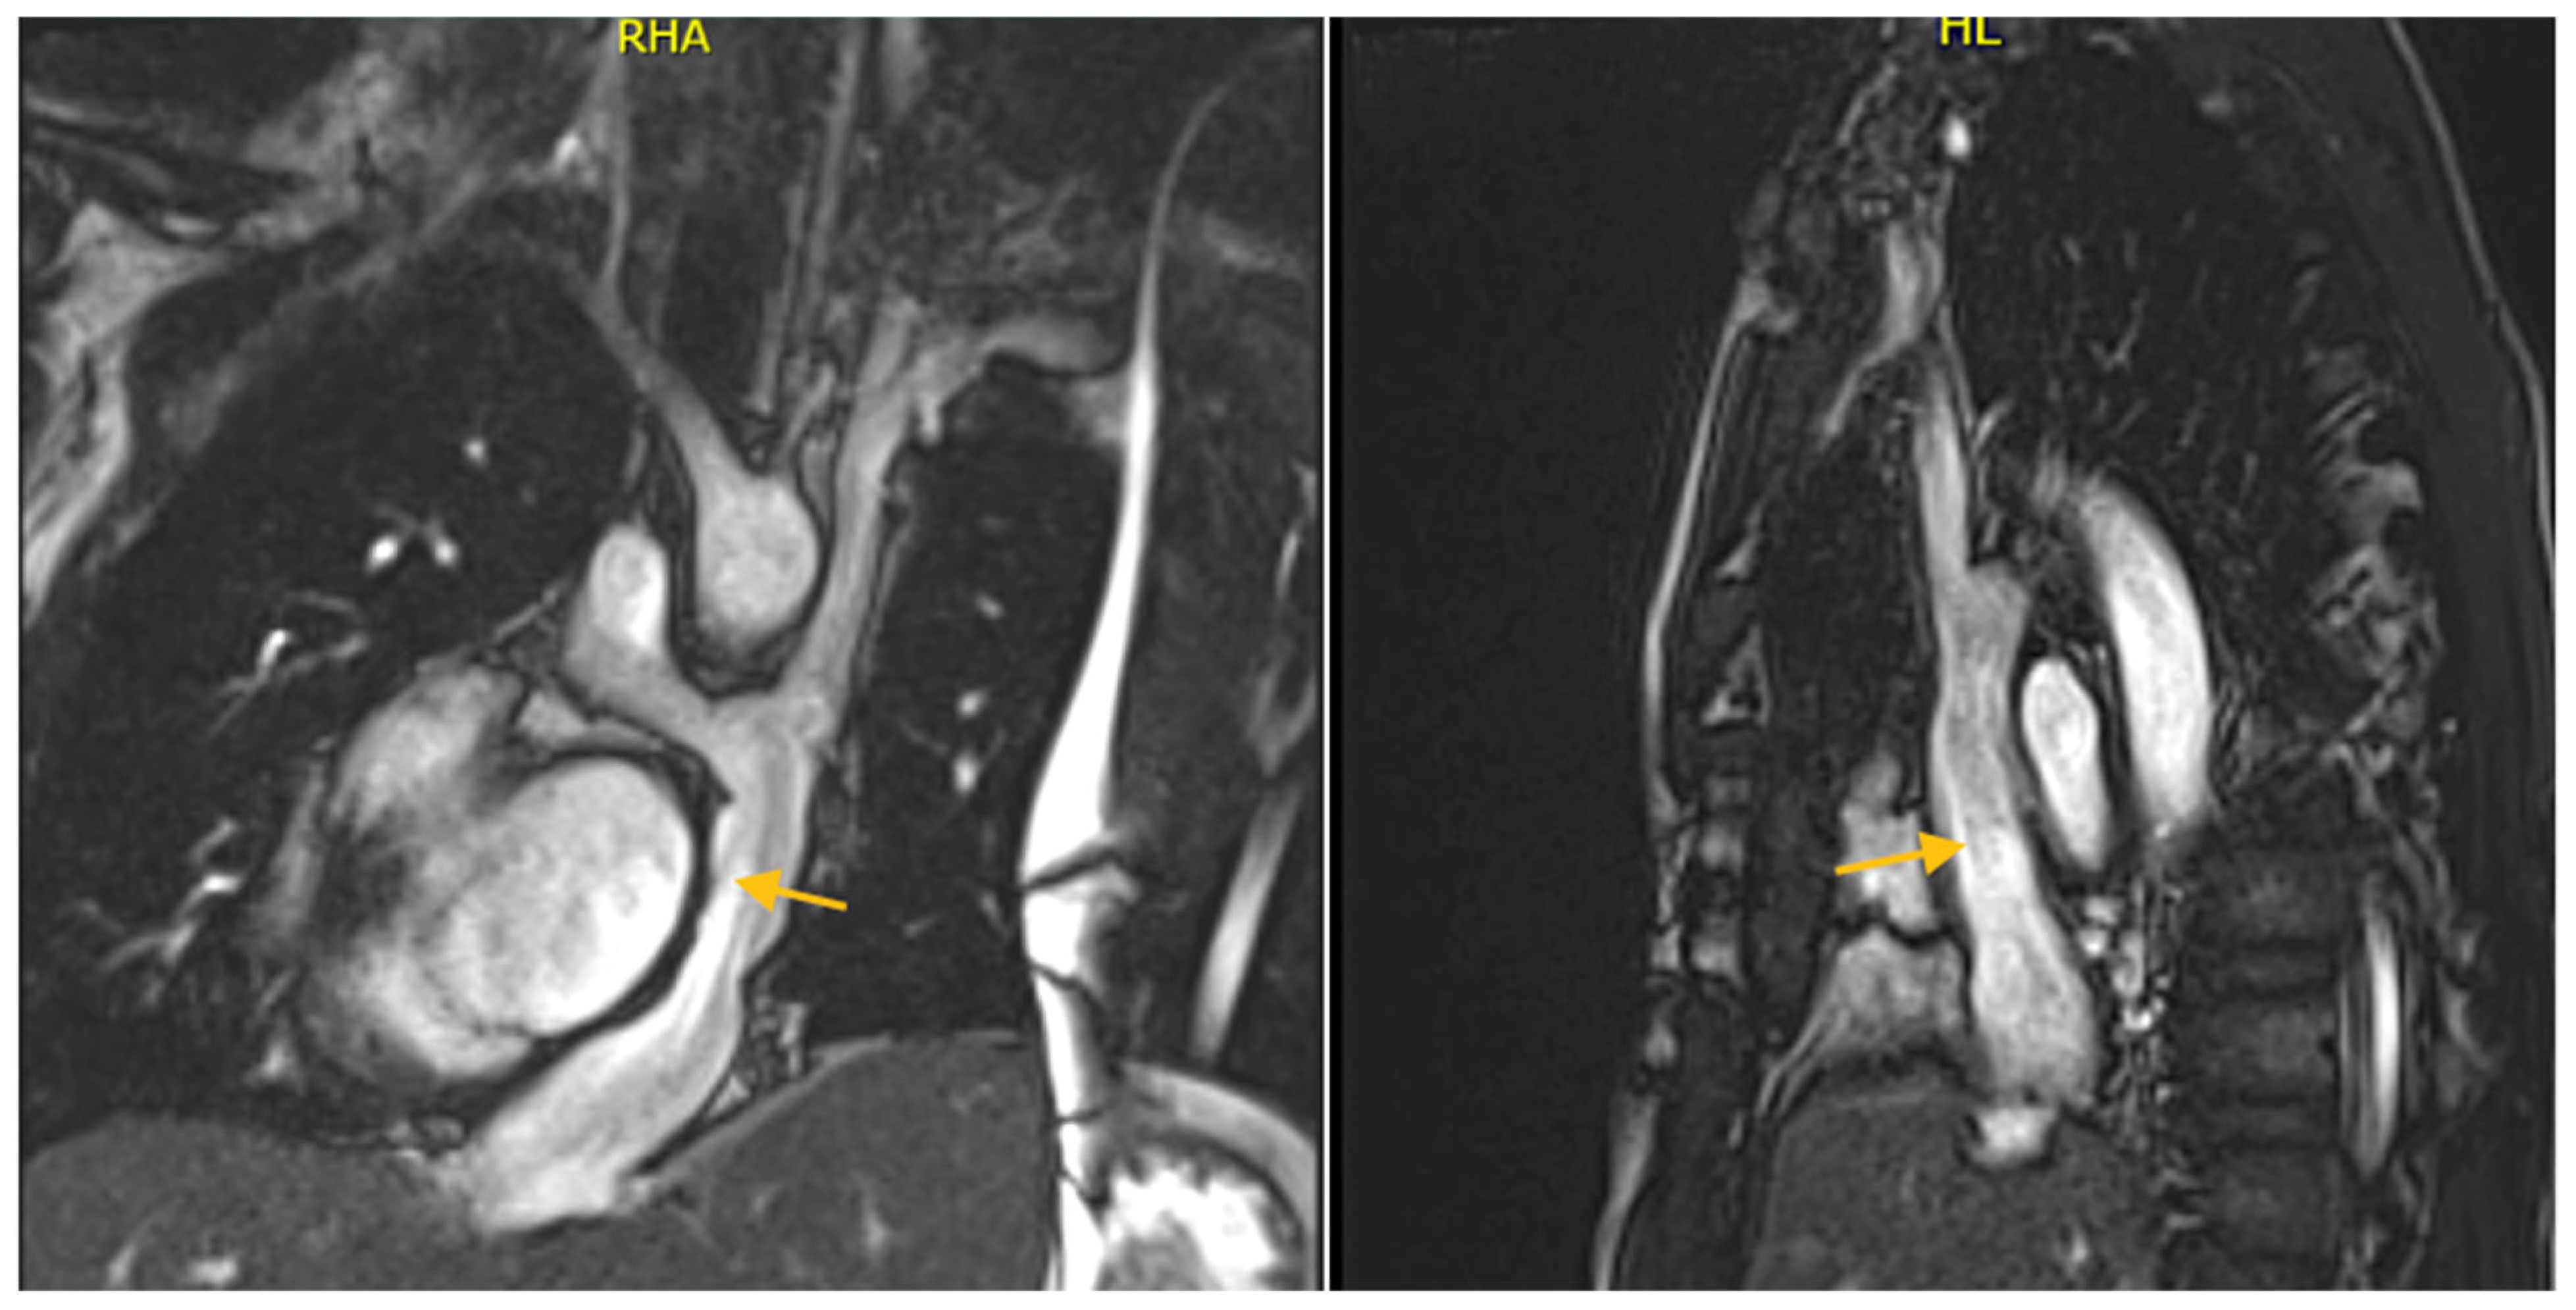

4. Multimodal Assessment During Pediatric and Adult Life Post-TCPC Completion